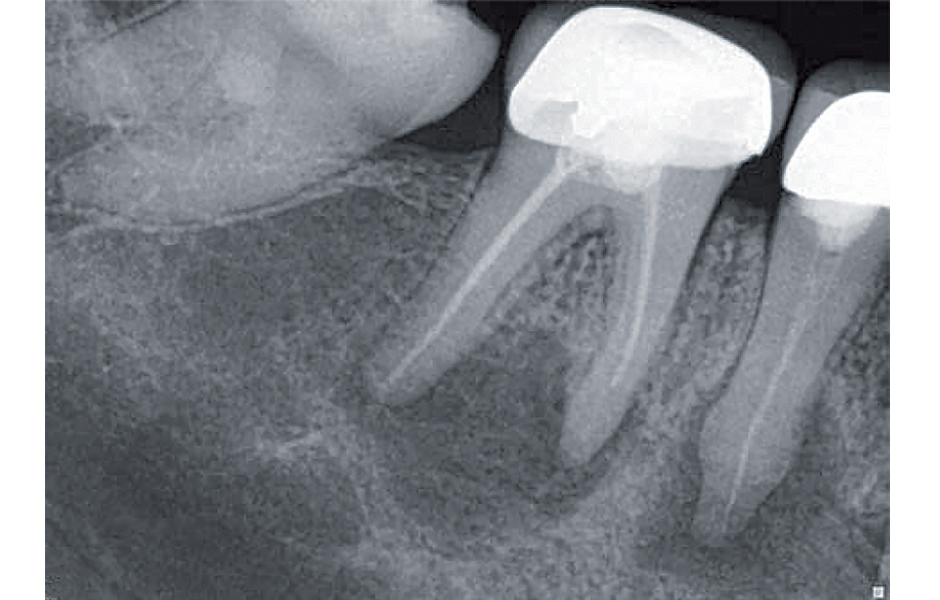

Druhá šance – reendodoncie

Jako zubní lékaři často čelíme nutnosti revidovat ošetření kořenových kanálků kvůli problémům, jako je například netěsnost výplně nebo neadekvátní předchozí léčba. Náš imunitní systém naštěstí hraje zásadní roli při udržování křehké bakteriální rovnováhy bojem proti bakteriální agresi. Někdy zůstává tato rovnováha nenarušena, bakteriální aktivita je omezena na apikální oblast a nejsou patrny žádné příznaky. Pokles naší imunitní reakce nebo zásahy do struktur endodonticky ošetřeného zubu novými výplněmi či korunkovými náhradami však mohou tuto rovnováhu narušit a vést k patologickým klinickým projevům.

Reendodoncie představuje různé výzvy v závislosti na faktorech, jako je kvalita původního ošetření, materiály použité k obturaci, přítomnost nerovností nebo zalomených nástrojů v kanálku, složitá anatomie kořenových kanálků, nutnost odstranění kovových či kompozitních čepů ad. Při přistoupení k reendodontickému ošetření je užitečné rozdělit postup do fází a systematicky řešit jednotlivé problémy od koronární části směrem k apexu. Postupné odstraňování jednotlivých překážek umožňuje efektivní zvládnutí celého procesu a dosažení požadovaného výsledku.

K reendodontickému ošetření používám nástroje Traverse a ZenFlex (Kerr Dental). Konkrétně orifice opener Traverse 25/.08 o délce 17 mm spolu s nástroji ZenFlex 35/.06, 30/.06 a 25/.06 (obr. 1). Tyto nástroje se vyznačují jedinečnou variabilní tepelnou úpravou, ostrými břity a speciálním designem drážek, díky čemuž jsou ideální jak pro prvotní endodontické zákroky, tak pro reendodoncii.